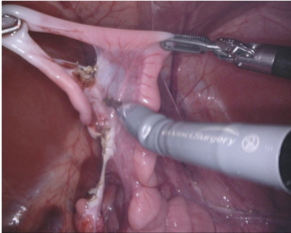

Our challenge was made up of 3 sub-problems. The first was binary instrument segmentation, where each frame was separated into da Vinci Xi instruments and a background class, which contained an ultrasound probe, surgical clips and porcine tissues. The second task was instrument part segmentation, where we scored the participants on whether they could correctly segment each articulating part of the instrument (see Fig. 3). Our final task was to segment and classify the instruments (see Fig. 4).

We provided the first 225 frames of 8 sequences as training data and kept the last 75 frames of those 8 sequences as test data. 2 of the full 300 frame sequences were kept as test sequences. Test labels were kept hidden from the participants. Our datasets contain 7 different robotic surgical instruments. The Large Needle Driver, Prograsp Forceps, Monopolar Curved Scissors, Cadiere Forceps, Bipolar Forceps, Vessel Sealer and additionally a drop-in ultrasound probe, which is typically held in the jaws of the Prograsp Forceps instrument. Samples from the training datasets are depicted in Fig. 2 and examples of the different instrument types are shown in Figure 3 and 4.